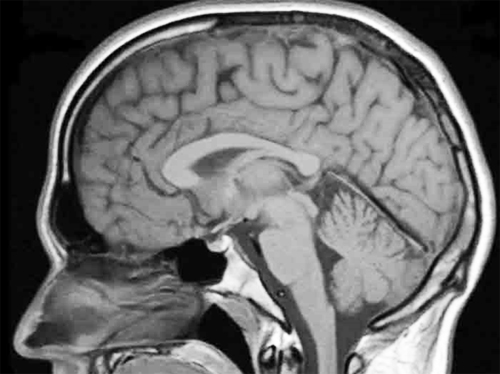

Le cerveau reste conscient après votre mort, ce qui signifie que vous savez que vous êtes mort, selon une étude

Votre cerveau restera conscient pendant quelques minutes après votre mort, a averti un éminent neuroscientifique.

Des chercheurs de New York ont découvert que les fonctions cérébrales peuvent continuer après l’arrêt du cœur – ce qui signifie que vous pourriez savoir que vous êtes en train de mourir après votre mort physique.

Les scientifiques ont découvert que la fonction cérébrale se poursuit dans le cerveau, la partie qui vous garde conscient, après l’arrêt du cœur.